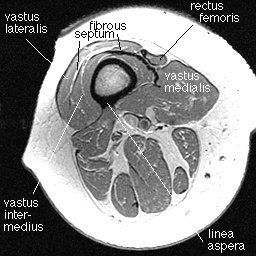

In the distal thigh, the anterior muscles are the four parts of the largest muscle group in the human body: the quadriceps group. We can see these parts in the image below. Only the distal most portion of the rectus femoris is shown, just before it merges with the thick dark band of the quadriceps tendon. This tendon is continuous with a fibrous septum that separates the vastus lateralis from the vastus intermedius.

Note the linea aspera, a ridge running down the posterior margin of the femur. The linea aspera is a popular muscular insertion site. In this image one can see the vastus intermedius and vastus lateralis inserting there, and the short head of the biceps femoris originating there.

As one travels distally down the thigh, the vastus lateralis and vastus medialis insert on the quadriceps tendon, as well as along the lateral and medial margins of the patella, helping to form the lateral and medial fibrous retinaculum around the patella.